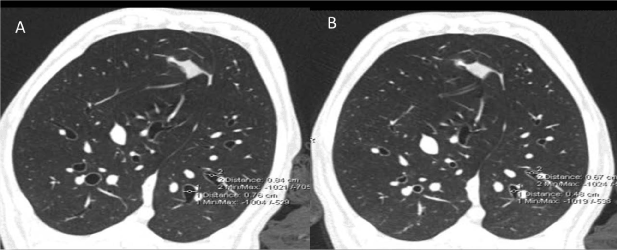

Figure 4: A. As a demonstration of the effect of our positive control (A) Methacholine dramatically Constricts airways prior to ablative intervention (B)

Functional evidence of effect on smooth muscle cells in the lung was determined by measuring airway dimensions pre and post ablation, as well as the response to methacholine. We also demonstrated the reverse of the methacholine response with the use of atropine (Figure 5-6, Table 2).

Pre-ablation control vs Pre-ablation MCH Constricts Airways (diameter cm)

Location 1

0.84 control to 0.67 post-MCH (-23%)

Location 2

0.76 control to 0.48 post MCH (-37%)

Experimental:

Pre-ablation MCH vs Post-ablation MCHMCH (diameter cm)

0.76 to 1.14 (+50%)

0.76 to 1.19 (+57%)

The positive control demonstrates the efficacy of methacholine to induce bronchial constriction, in normal (pre-ablation) airways.  The experiment demonstrates the effect of ablation to acutely impair the bronchoconstrictive response of MCH, measured before and after ablation. Airway measurements made at 15 cm of PEEP during a breath hold at under I.V. anesthesia with neuromuscular blockade.